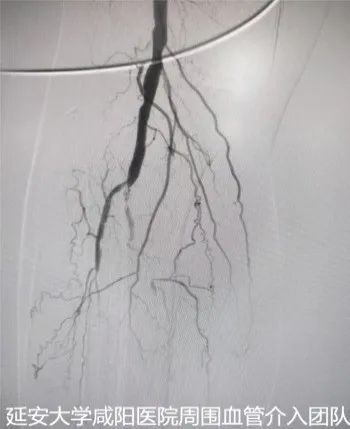

术前DSA